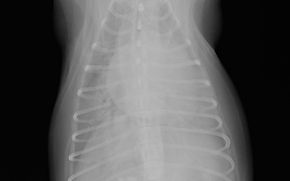

フィラリア症